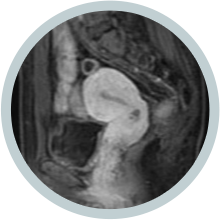

• 시술 6개월 후 시술 6개월 후

하이푸 시술 6개월 후 MRI 조영증강영상에 절제된 근종이 유의하게 축소됨

• 시술 1년 후 시술 1년 후

하이푸 시술 1년 후에 절제된 근종이 유의하게 축소됨을 보임